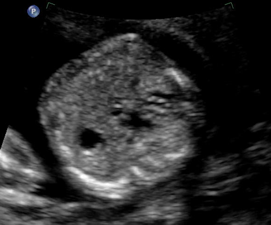

Above. Case 3. 28 3/7 weeks gestation. Longitudinal view of a cyst in the right upper quadrant. Note the close proximity of the cyst to the fetal spine. On MRI, the kidney is displaced inferiorly and given the potential retroperitoneal location, a duplication cyst of the gastrointestinal tract is a possibility.